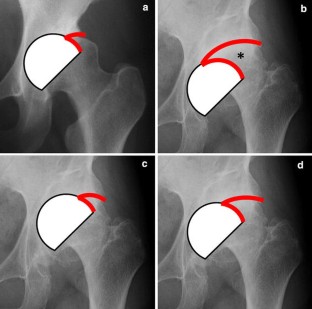

Fig. 3